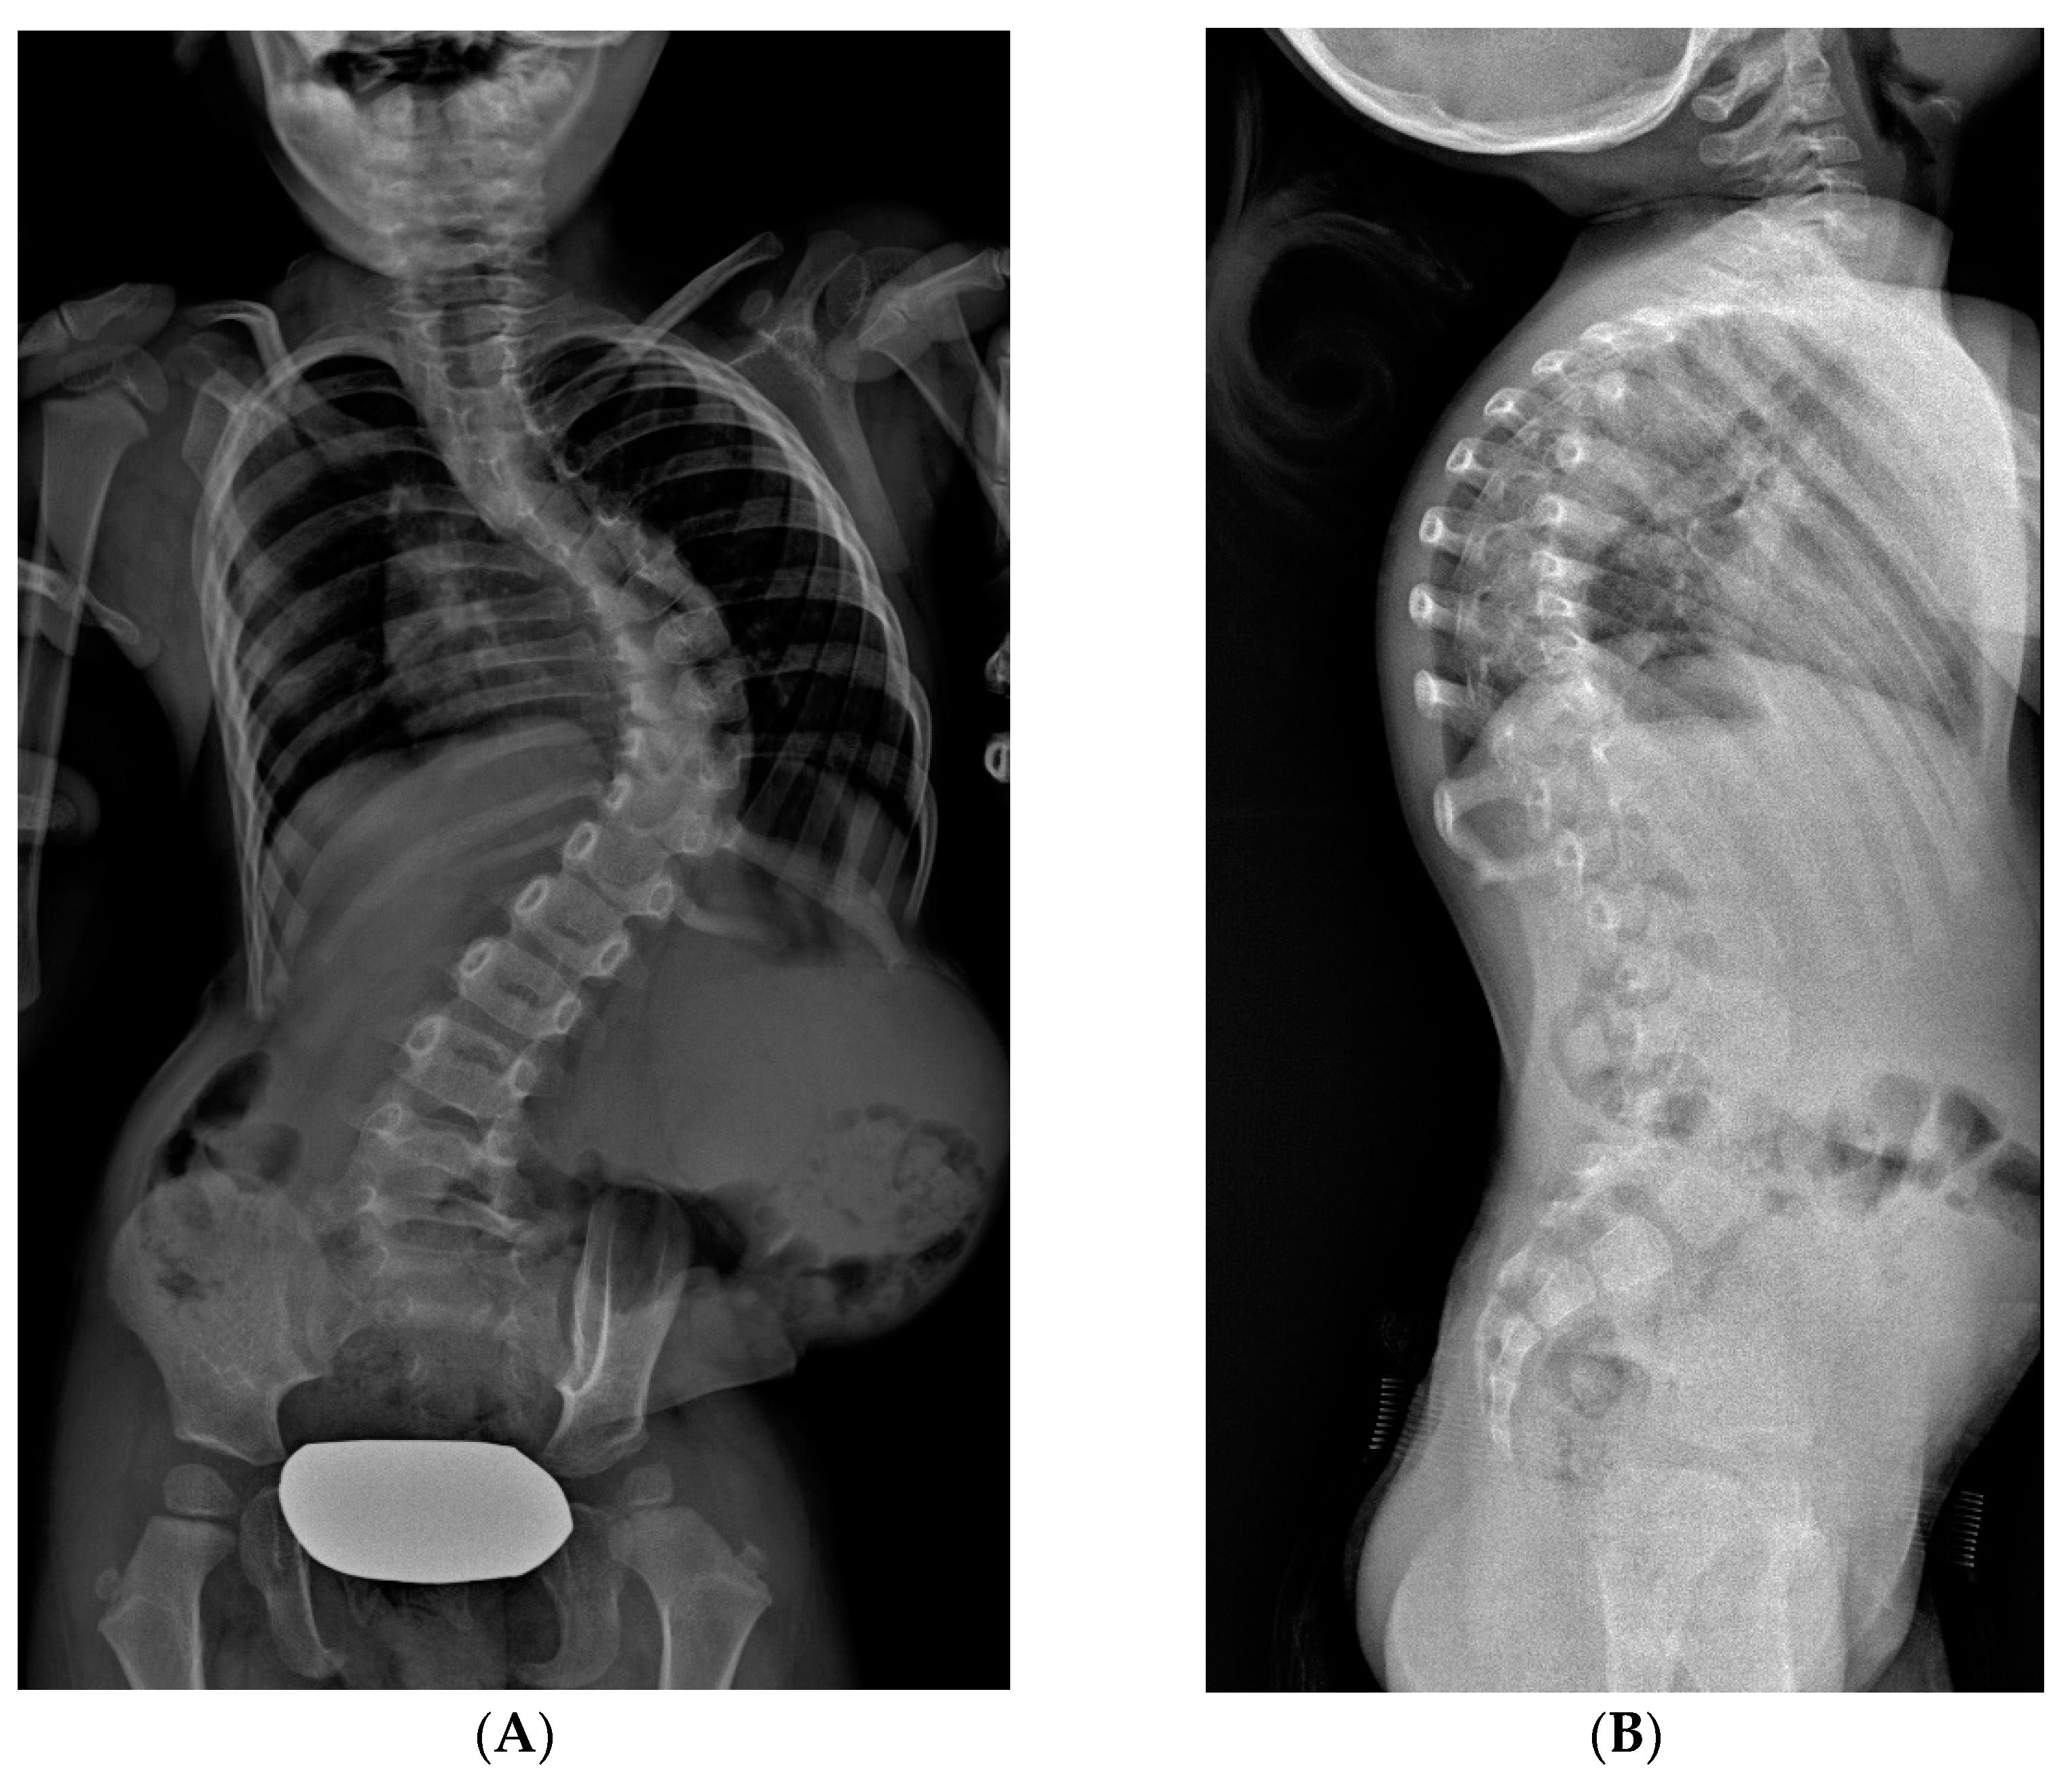

Figure 6.

X-rays of early onset scoliosis (EOS) corrected with vertical expandable prosthetic titanium rib (VEPTR): (A) pre-operative antero-posterior X-ray view; (B) post-operative antero-posterior X-ray view; (C) pre-operative lateral X-ray view; (D) post-operative lateral X-ray view.

VEPTR is a titanium alloy longitudinal rib distraction device. As with growth rods, repeated lengthenings are required [21]. The goal is to maximize thoracic volume and symmetry of the deformed thorax by lengthening the constricted hemithorax through a transverse opening wedge thoracostomy of the concave side [22], either through osteotomy of fused ribs or intercostal muscle lysis. The scoliosis is corrected indirectly by the thoracostomy, and the thoracic reconstruction is stabilized by the addition of a rib-to-spine or rib-to-pelvis VEPTR construct and another rib-to-rib VEPTR. No bracing is used postoperatively. VEPTRs are lengthened every four to six months. As 50% of the final thoracic volume depends on the growth between the age of 10 to 15 years, the final fusion is preferentially delayed until skeletal maturity (Figure 5 and Figure 6). When spinal deformity is associated with severe thoracic deformity, VEPTR is indicated. The main feature of this technique is that proximally, the bar is anchored to the ribs. Lengthening required surgery room, on average, every 12 months.